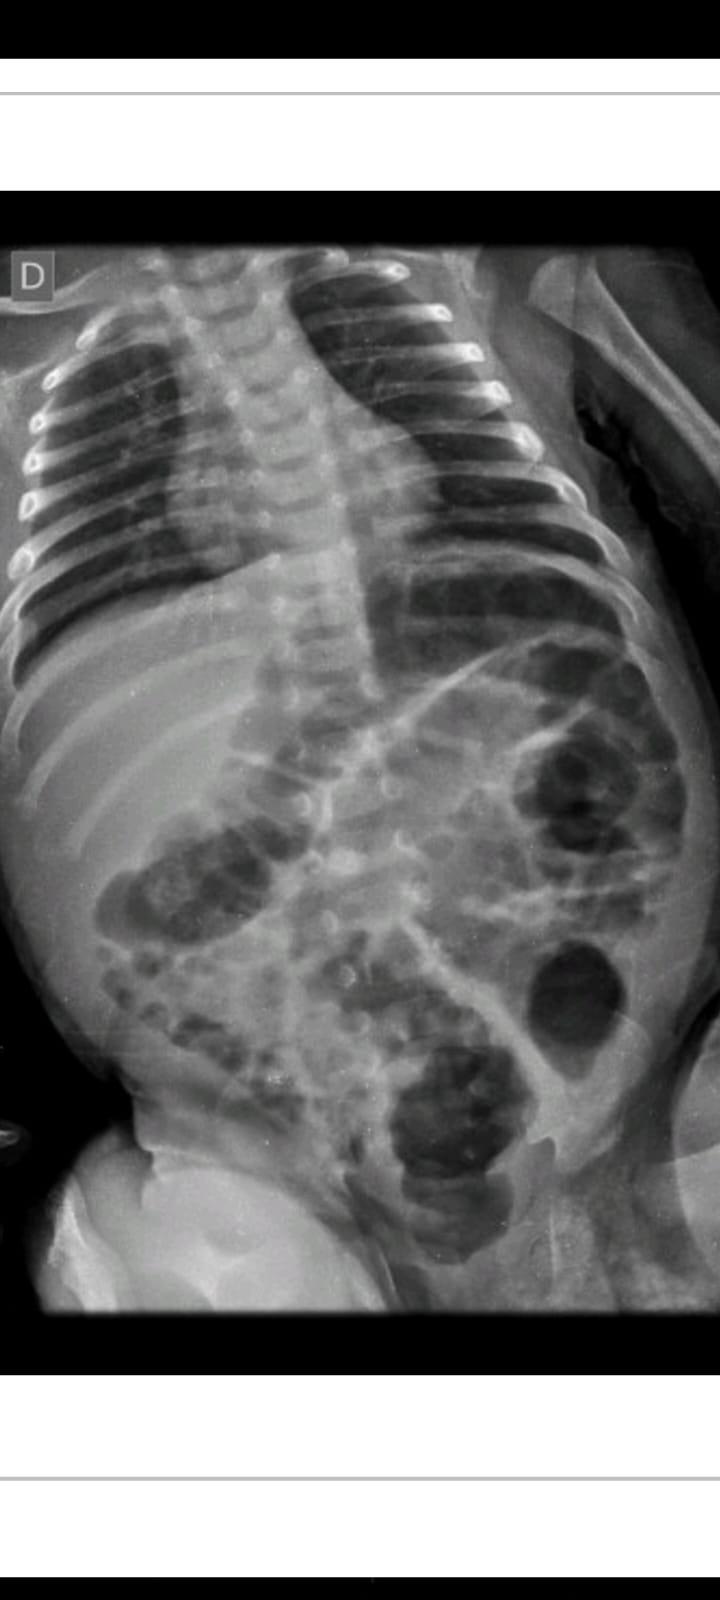

A criança, um menino, apresentava além de vários hematomas e escoriações pelo corpo, em exames aprofundados se constatou lesões ósseas em uma das tíbias, em um antebraço, além de costelas.

Laudo Médico apontou ainda que tais ferimentos expuseram o menino a risco de vida.